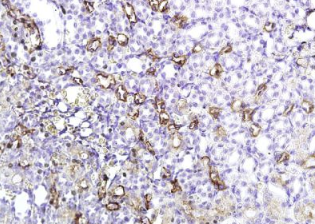

组织/细胞:大鼠肾组织;4%多聚甲醛固定石蜡包埋;

抗原提取:柠檬酸缓冲液(0.01M,pH 6),15min煮沸,用3%过氧化氢阻断内源性过氧化物酶30min;37℃下阻断缓冲液(正常山羊血清)20 min;

孵育:抗AQP-1多克隆抗体,未结合1:400,在4°C下过夜,然后与二级抗体结合,DAB染色。